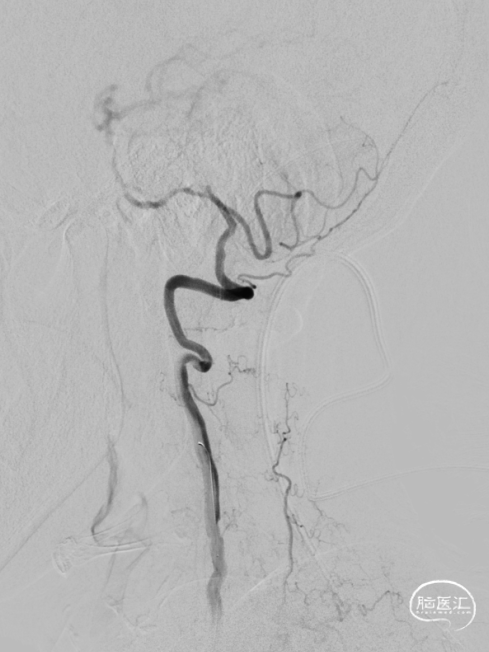

全脑血管造影DSA:双侧椎动脉起始段狭窄。远端供血不足。

患者双侧椎动脉均狭窄,左侧重度狭窄。左侧椎动脉充盈延迟、血流瘀滞,为闭塞前表现。所以权衡双侧椎动脉狭窄血管成型术的指征,优先处理左侧椎动脉起始段狭窄。为预防急性后循环缺血性卒中,在家属知情同意前提下行支架成形术。

该患者双侧椎动脉起始段均狭窄,左侧更为严重,为闭塞前病变。为预防致死致残性脑卒中,行左侧椎动脉起始段支架植入术。选择Bridge椎动脉雷帕霉素靶向洗脱支架。该支架的雷帕霉素涂层可向血管内膜靶向释放药物,有效抑制支架植入术后的内膜增生,减少远期支架内再狭窄几率。同时也能有效改善后循环的血供,减少后循环脑卒中发生机会。该支架是治疗椎动脉狭窄的良好选择。